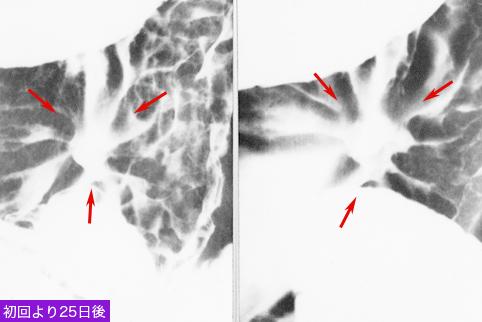

疾患(病理主体)の分類悪性上皮性腫瘍/腺癌

部位(臓器別)胃(部位)/体部

検査方法X-P

腫瘍の肉眼分類0型(表在型)/III型(III+IIc)

病変の最大径(ミリ)20〜24

腫瘍の深達度m